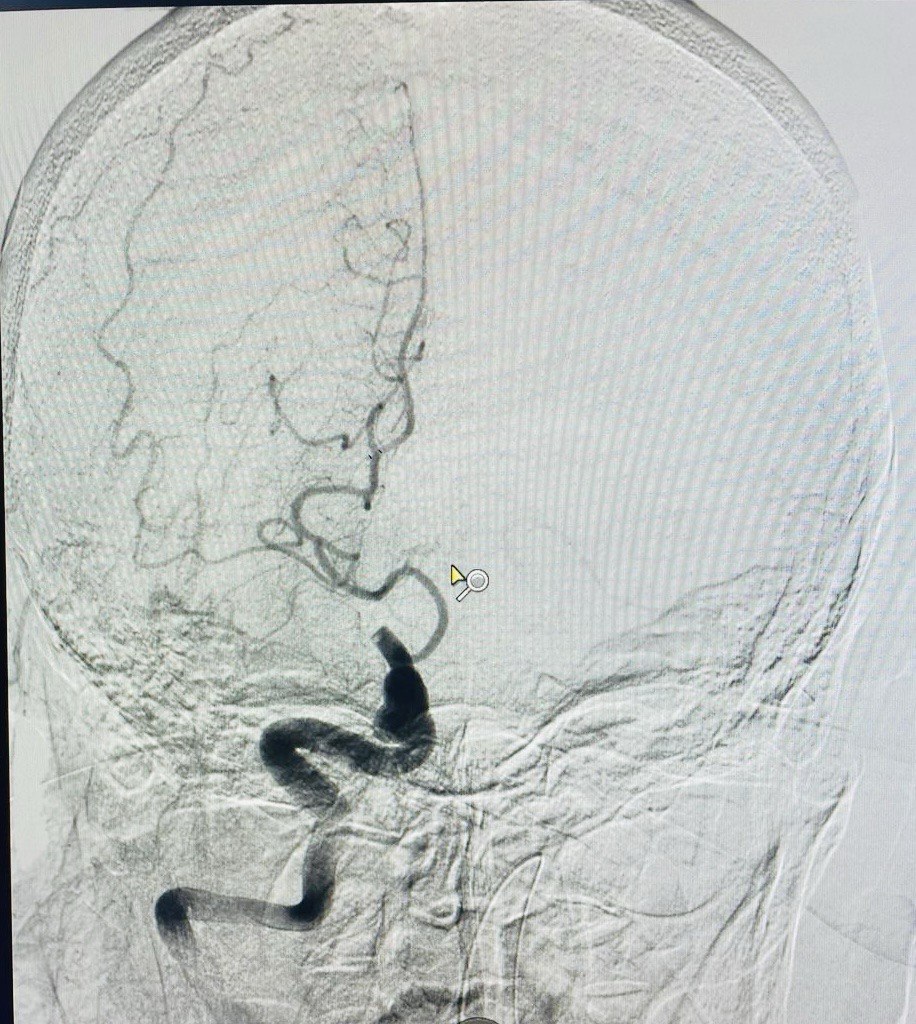

Екстракція тромбів із судин головного мозку

Що таке стентування сонних артерій

Стентування сонних артерій (CAS) – це процедура, яка виконується для відкриття звуженої сонної артерії. Вона полягає і розміщенні стенту (сітчаста трубка) в звужену артерію. Ця процедура також називається каротидною ангіопластикою.

Є дві сонні артерії (по одній з кожного боку шиї), які кровопостачають мозок. Ці артерії можуть бути звужені та пошкоджені жировими відкладеннями (атеросклеротичними бляшками). Ця бляшка може обмежити приплив крові до мозку, що підвищує ризик інсульту.